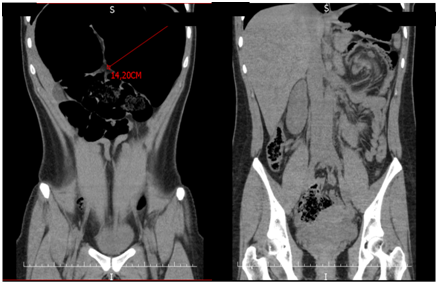

A 16 year-old girl complaining of chronic constipation and abdominal bloating since early childhood presented in the emergency department with a 36-hours of abdominal pain. The plain abdominal radiograph showed dilated small and large bowel (Figure 1). A simple abdominal CT scan revealed a dilated transverse colon (14.2 cm) and a whirl sign (Figure 2). A diagnosis of a transverse colonic volvulus was done and the patient was scheduled for a surgical intervention. A laparoscopic approach was done and a transverse colonic volvulus was detorsed. The patient had an uneventful recovery and was discharged home. During her follow up, chronic constipation and abdominal bloating continued to be occasionally present, with no improvement with dietary changes and conservative measures. A follow up CT scan confirmed the presence of a dilated transverse colon. We then decided to perform an open transverse colonic resection with a primary anastomosis (Figure 3). She was discharged home on the fifth postoperative day. One-year follow up has shown no recurrence of symptoms.

Figure 2 CT Transverse colon dilatation and a whirl sign.